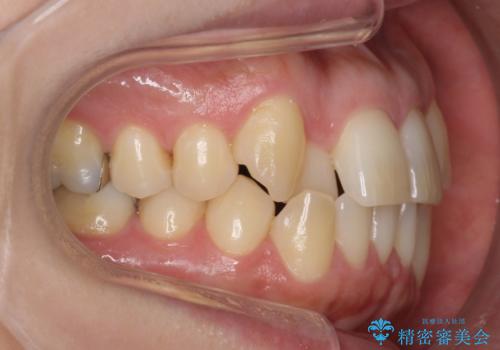

- 前歯のガタガタを主訴に来院。

・正中を顔にしっかり合わせるには、上下左右4本抜歯

・出来るだけ合わせる程度でよければ、左のみ上下2本抜歯。但し上下正中は揃わないかもしれない。

を提案し、

2本抜歯を選択されました。

上の前歯が内側に入っているクロスバイトは、笑った時に影になってしまい、かなり目立ちます。

内側に入っている前歯を外に出すだけで劇的に印象が変わります。